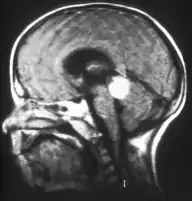

Retinoblastoma

El retinoblastoma es un tumor canceroso que se desarrolla en la retina causado por una mutación en la proteína Rb, codificada por un gen supresor tumoral denominado RB1.[1] Este tumor se presenta en mayor parte en niños pequeños y representa el 3% de los cánceres padecidos por menores de quince años. Constituye la primera causa de malignidad intra-ocular primaria en los niños y la incidencia anual estimada es de aproximadamente 4 por cada millón de niños.[2]